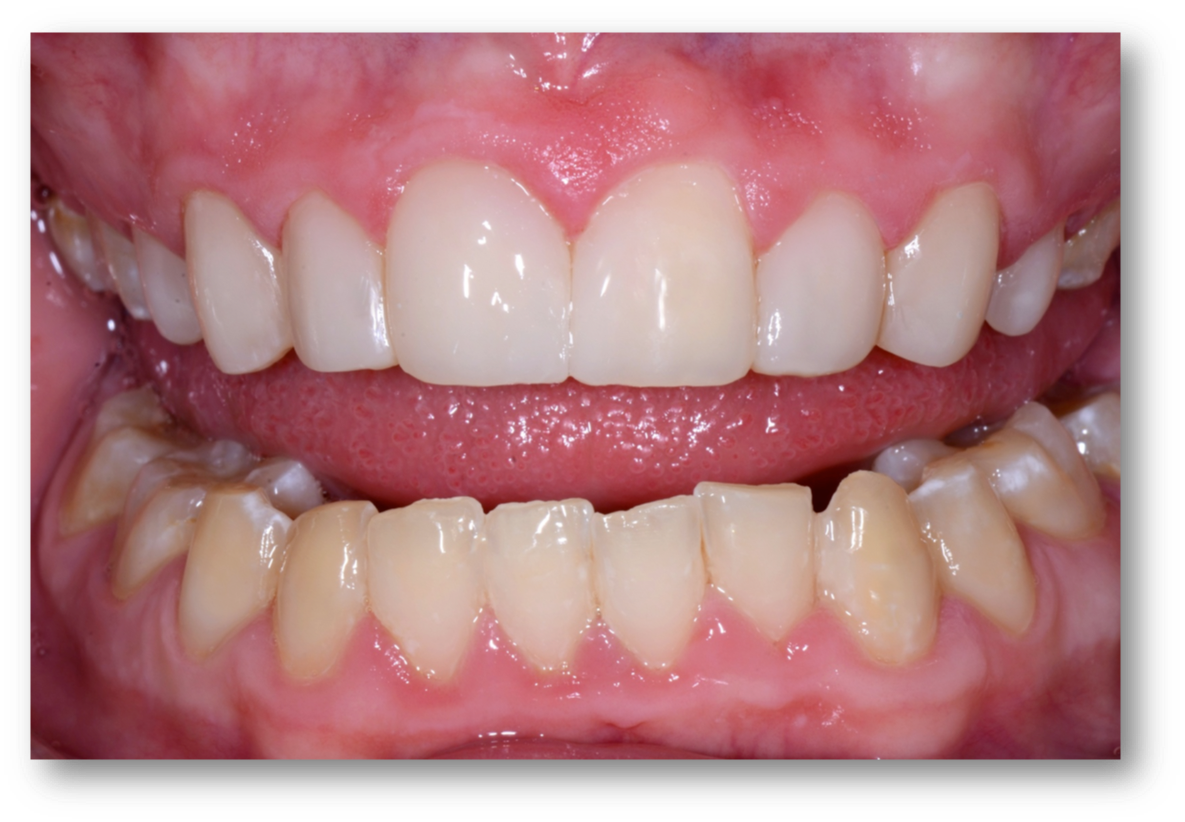

Example 1: Soft-Tissue Recontouring and Esthetics

The first example is of a mouth that needed soft-tissue recontouring with better esthetics (Figure 1). A diode laser is important for debridement, soft-tissue engineering, and better cleaning afterwards. The diode laser is popular in dentistry due to its small size and ease of use for minor soft-tissue surgery.1 It is a minimally invasive technology that offers advantages superior to those of the conventional scalpel, such as reduction of bleeding and inflammation and the lower probability of scars.2 Its effectiveness is comparable with that of other types of lasers, and it is an option of lower cost and greater ease of use.  Based on its photothermal effect, the diode laser is used for the removal of small lesions of the oral mucosa by excision or vaporization procedures.3

Fig 1. A patient was in need of soft-tissue recontouring and better esthetics.

Figure 1

Fig 2. Same patient, 5 weeks later.

Figure 2